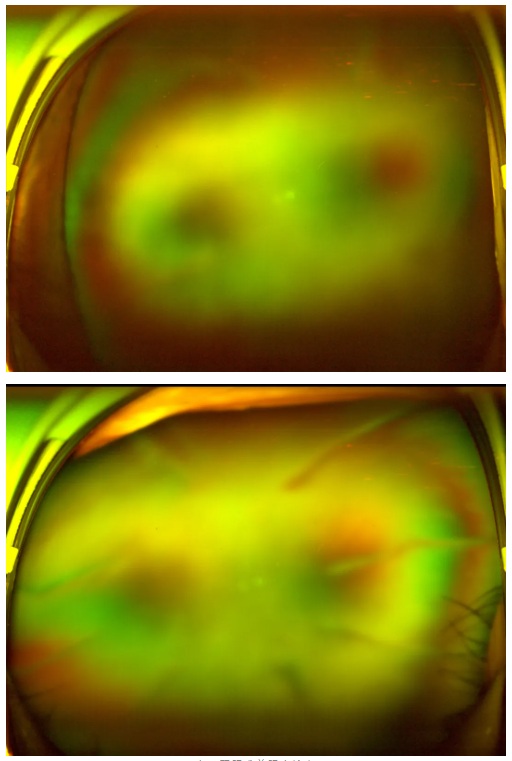

老王雙眼術(shù)前眼底檢查

糖尿病視網(wǎng)膜病變